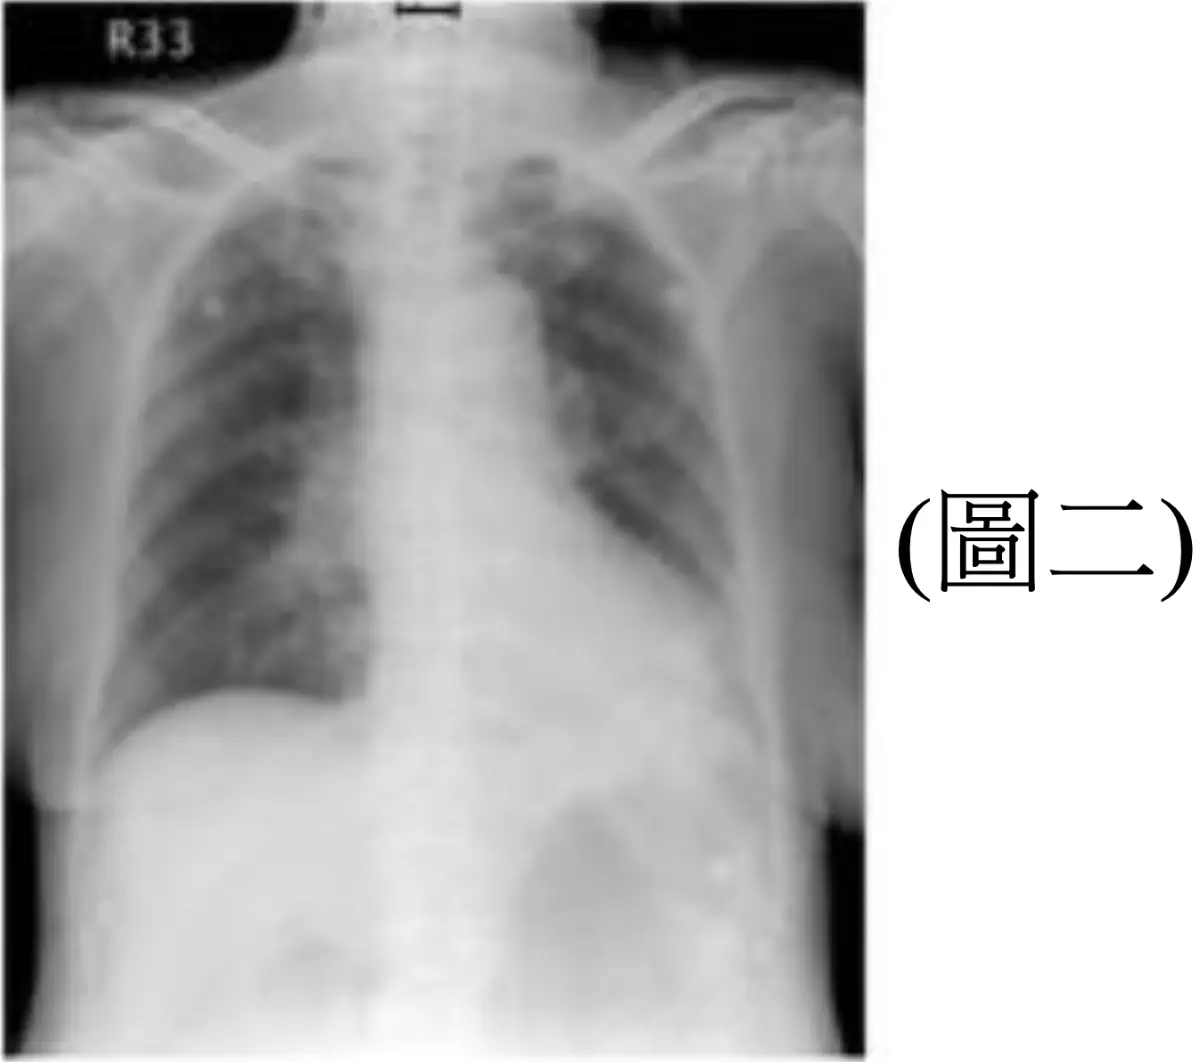

一位 82 歲女性,二天前灌食時發生嗆咳,今日因發燒、喘咳,被家屬送來醫院治療,病人神智不清,血壓90/50 mmHg,心跳130次/分,呼吸喘促,聽診肺部多痰音,來院後所照胸部X光如(圖二)、氣管及鼻胃管位置解析如(圖三),此時不宜進行何項處置?

• 兩天前灌食時嗆咳,今日發燒、咳喘,胸部 X 光呈右下肺大片浸潤,符合吸入性肺炎。